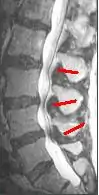

Since an MRI provides excellent imaging of blood vessels and tissues, it is recognized as the best type of imaging to observe signs associated with lumbar compression. The precise measurement of the diameter of the spinal canal is a particularly important component when determining the severity of the stenosis itself.[2] High strength 3-Tesla MRI machines are being utilized due to the increased vascular imaging capabilities. Better resolution capacity allows for more detailed observations by the healthcare provider. The sharp contrast of the high power MRI outlines details in the vertebra that are critical when examining a patient with lumbar spinal stenosis who may need a laminotomy.[1] MRI scanning post invasive surgery is used to see the quality of the surgery itself, yet the appropriate postoperative time elapsed before conducting an MRI is a debated topic.[2]

A CT scan is not the most effective imaging technique when observing lumbar abnormalities, however it can supplement an MRI by detecting certain degenerative processes. When determining whether or not a laminotomy will be beneficial for the patient, a healthcare provider must assess the severity of the possible abnormalities. Out of all the potential reasons to have a laminotomy performed, lumbar spinal stenosis is the chief reason. CT scans are used specifically to pinpoint a buckled lumbar ligamentum flavum as well as facet hypertrophy, which are some of the main pathophysiological changes indicative of lumbar spinal stenosis.[2] Even though a CT scan can reveal these pertinent signs of lumbar spinal stenosis, it can sometimes give a cloudy image due to the shadowing of the tissue contrast. When this occurs, an intrathecal myelography contrast is conducted with the CT scan to fix the abnormal contrast. A CT scan can also reveal an increase in the cross sectional area of the L3 vertebrae, which ultimately decreases the cross sectional area of the spinal canal.[2] As an increase in the size of the L3 vertebrae occurs, pressure builds up on the cauda equina, commonly causing pain in the lower back and lower extremities. Cauda equina compression can also be due to stenosis of L4-5 region as well.[1] Even though the CT scan allows for intensive image studying, the fixed nature of the image collection process alone is not enough to reach a definitive diagnosis of lumbar spinal stenosis. The outcome of the CT scan can help compile physiological evidence that the patient has lumbar spinal stenosis, and that the patient may potentially benefit from a laminotomy to improve his or her quality of life.[1]

Other than static imaging processes, a CT scan can also be used for observing changes in spinal canal features before and after a laminotomy. One of the main signs of lumbar spinal stenosis is the thickening of the ligamentum flavum, causing it to expand towards the spinal canal.[2] When observing the cross sectional area of the spinal canal of a human cadaver, it was found that the area had decreased due to ligamentum flavum thickening. The ligamentum flavum did not appear to alter the dynamic alterations in the dimensions of the spinal cord. Even after the intervertebral disc was removed, the ligamentum flavum did not appear to be a factor in the change in the dimensions of the spinal canal.[6] By understanding the magnitude of the role that ligamentum flavum hypertrophy plays in lumbar sacral stenosis, the necessity of an invasive lumbar spinal procedure can be accurately measured.